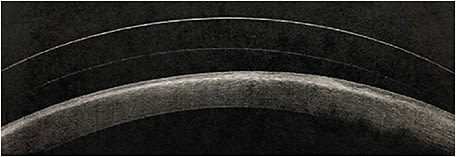

SND is diagnosed on discovery of gray-white to bluish raised subepithelial corneal lesions via slit lamp examination. These lesions typically are found in the peripheral to mid-peripheral cornea and may occasionally stain with fluorescein. On histological study, SND nodules show absent or broken Bowman’s layer that have overlying thinned epithelium and disorganized subepithelial collagen fibrils, and thick and tortuous branches of stromal nerves are found beneath SND nodules. Activated keratocytes also are found within the stroma posterior to the nodules, and elongated basal epithelial cells are seen at the peripheral edge of nodules. Deep stroma and endothelium are not affected in eyes that have SND. Of note: Corneal topography of SND eyes may reveal irregular astigmatism secondary to areas of raised lesions.